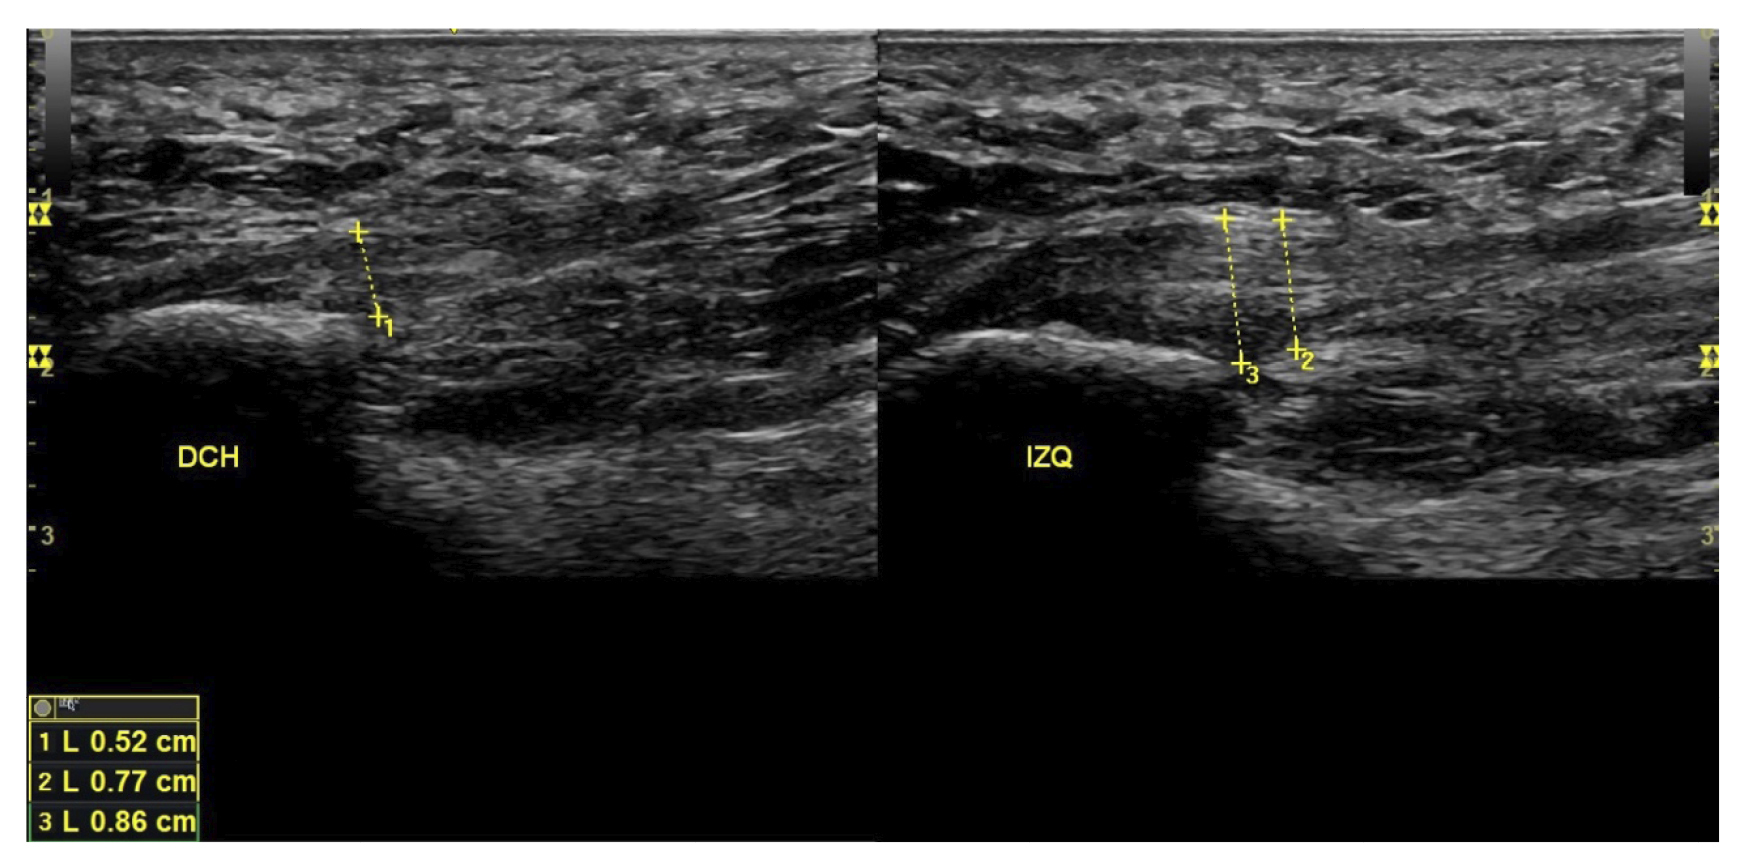

Variables utilizadas

A todos los pacientes se les realizó una evaluación clínica y una evaluación ecográfica. La evaluación clínica se basó en una escala analógica visual (EVA) (13) (0-10) y el índice de función del pie (FFI) (14,15), que evalúa la función en una escala de 0 a 100. También se clasificó a los sujetos como sedentarios, activos o deportistas en función a su actividad física diaria, así como si era la primera vez que aparecía la enfermedad, era una recidiva o era crónica(16). También se evaluó el sexo, el peso y la talla, la presencia de vascularización en la fascia plantar visualizada con ecografía en el momento de la evaluación inicial y la forma biconvexa(17) o aplanada de la fascia plantar (Figura 1).

Figura 1. Fascia plantar con morfología normal a la izquierda y fascia plantar con morfología biconvexa a la derecha.

El diagnóstico se estableció en base a los síntomas y se confirmó mediante ecografía con equipo de alta resolución (Alpinion Ecube 9, ALPINION MEDICAL SYSTEMS Co., Ltd., República de Korea) con transductor lineal de 6 a 12 MHz (Figuras 2 y 3).

Figura 3. Área de medición del grosor de la fascia plantar. La línea punteada corresponde con la medición del grosor.